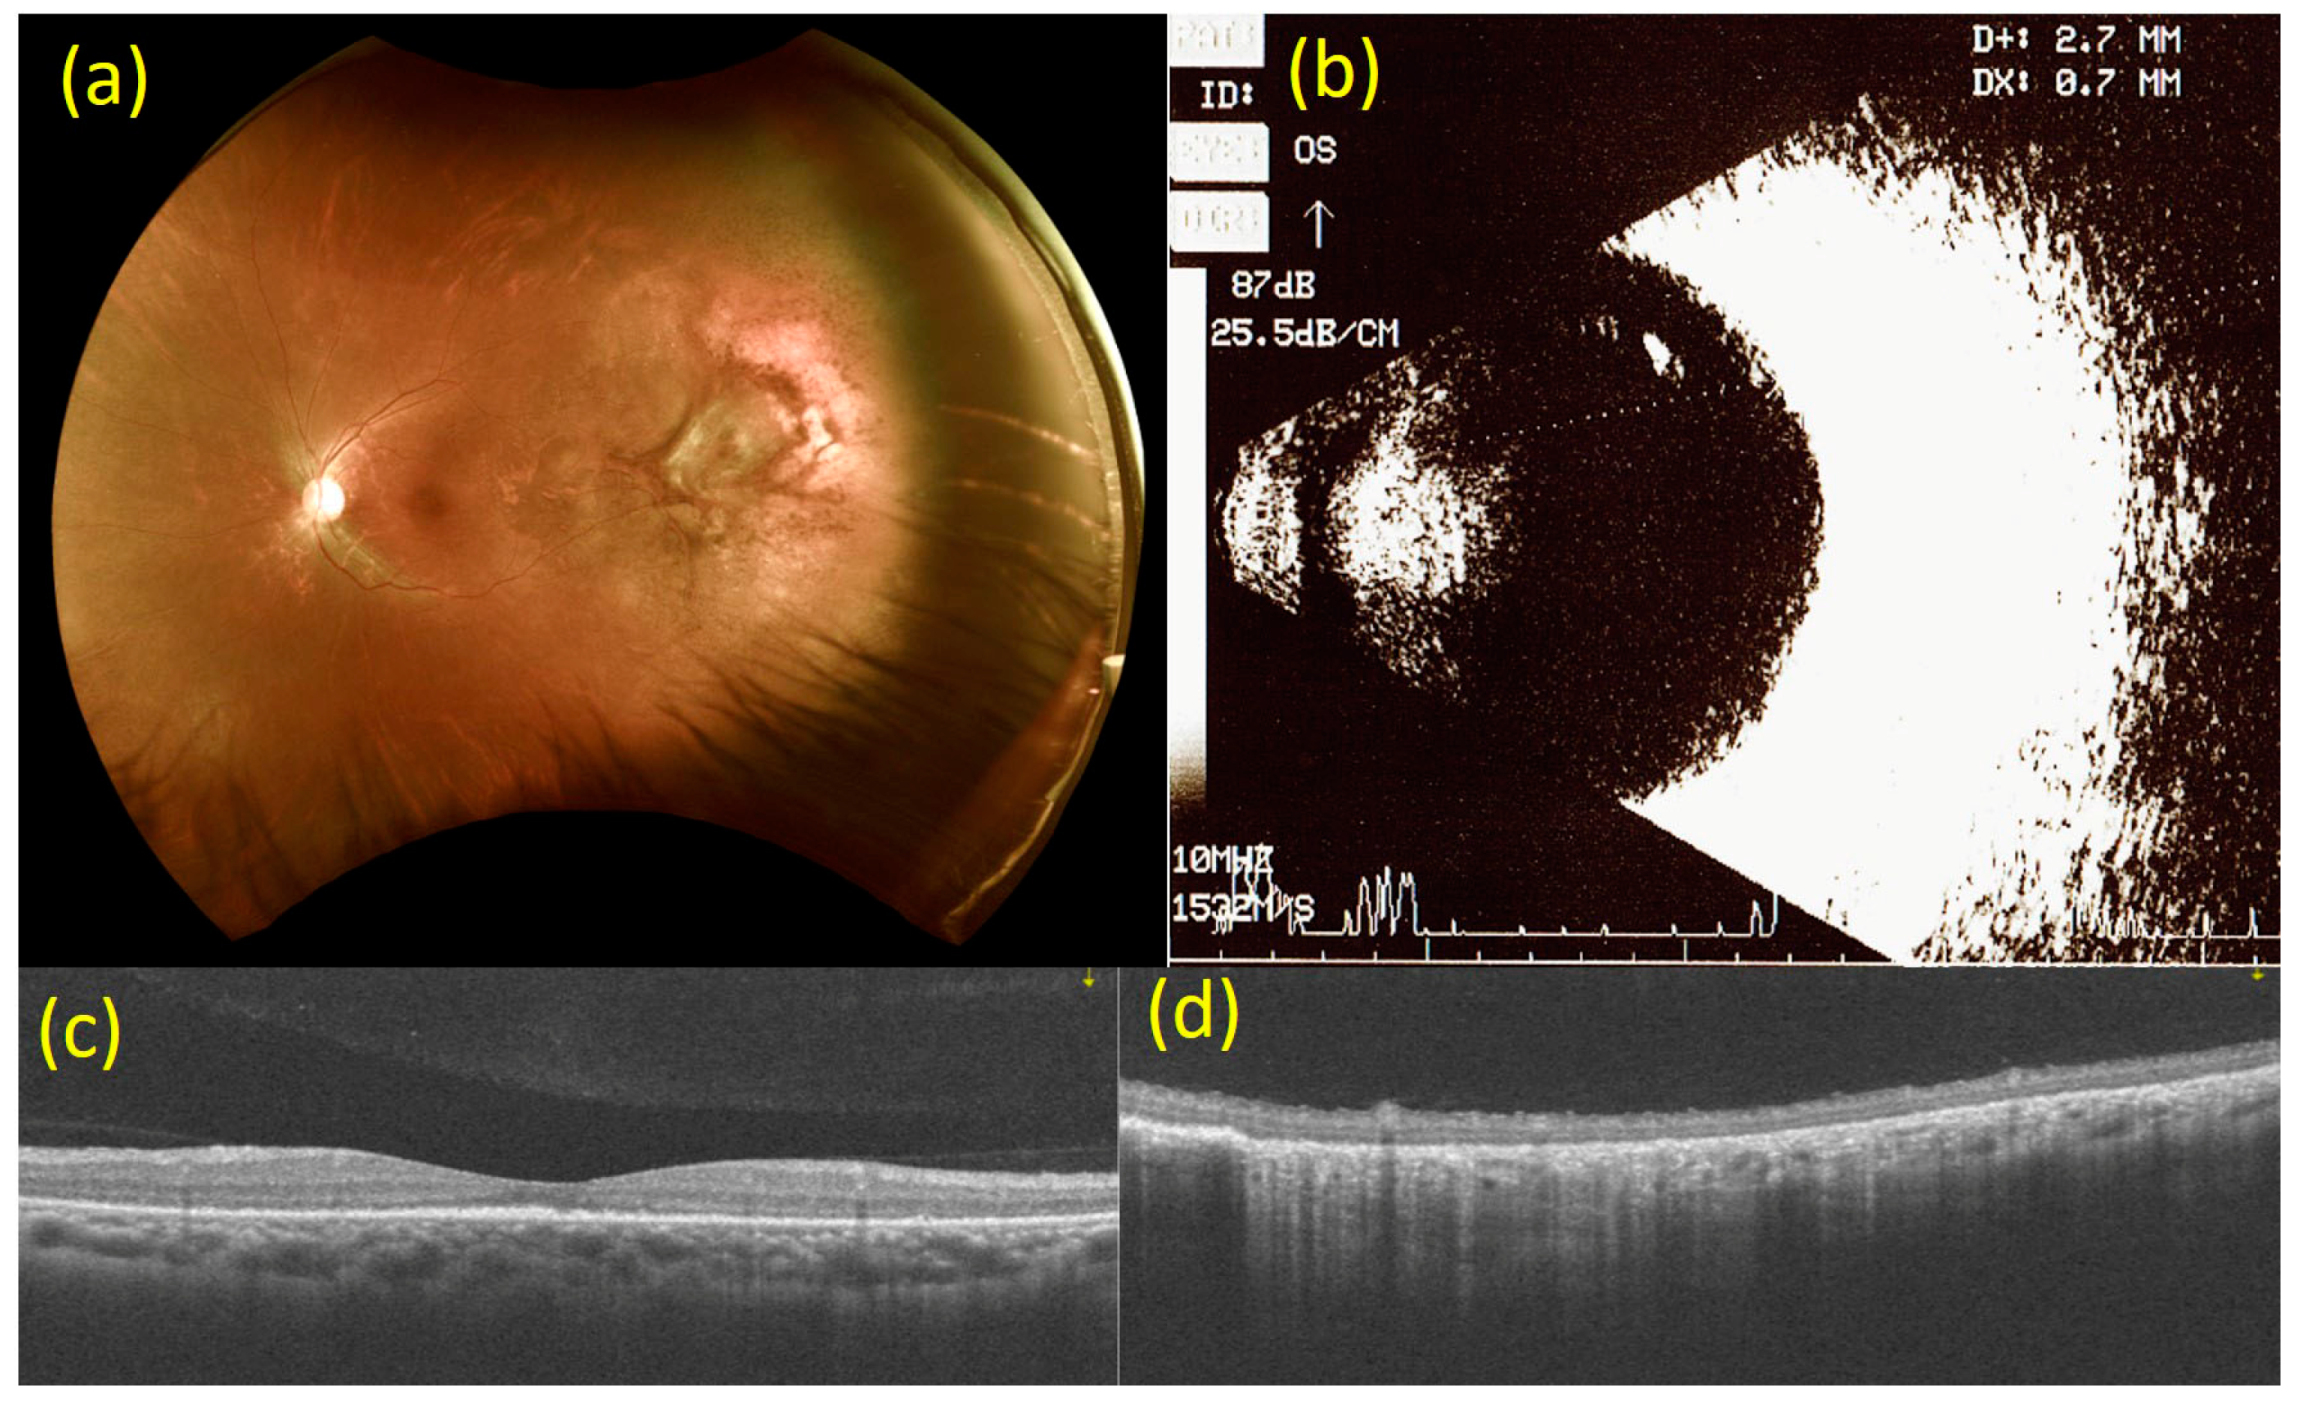

2. Case Report